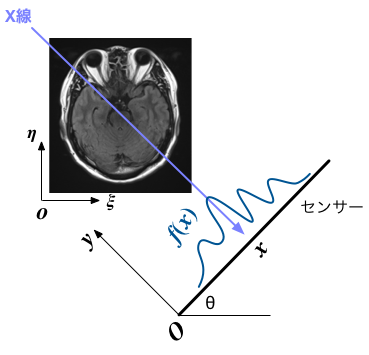

X線のように指向性と透過性の強い電磁波を物体に照射すると、内部の組成や密度に応じて吸収され、「反対側」で検出される信号の強度が変化する。 線源を並行移動しながらスキャンすることで、ある方向から見た、吸収の程度の分布を得ることができる。 センサーの方向角を $\theta$、センサー上の位置を $x$とし、その点での吸収率(信号強度から換算)を $f(\theta,x)$ と表すことにしよう。

図のようなセンサーを基準にした座標上で、計測対象となる物体の位置 $(x,y)$ での電磁波の吸収率を $\rho_{\theta}(x,y)$ とすると、 センサーに到達までのあいだに、電磁波はその経路に沿って累積された分だけ減衰するので、 $x$での減衰量は $$ f(\theta,x) = \int \rho_{\theta}(x,y) \, dy \tag{1} $$ となる。そして、この$\rho_{\theta}(x,y)$が我々が知りたい(見たい)データということになる。